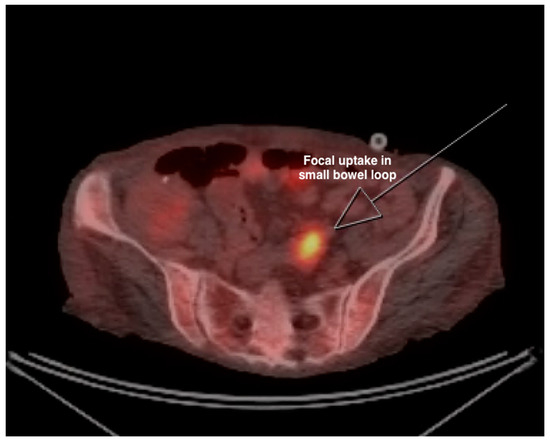

The biopsy was suggestive of metastasis from the gastrointestinal tract. The patient underwent an esophagogastroduodenoscopy and a colonoscopy to localize the primary tumor, but both procedures were unremarkable for any evidence of malignant lesions. A capsule endoscopy was also performed to assess the small bowel, but there was no evidence of any malignant lesions or active bleeding. In order to further localize the bleeding, a tagged RBC gastrointestinal scan was performed that showed a focus of increased tagged red blood cells along the splenic flexure and extending inferiorly towards the midline. A PET-CT was performed that showed a focal intense FDG uptake in the left upper quadrant in the small bowel loop and multifocal FDG avid hepatic metastasis (Figure 2 and Figure 3). Based on the PET-CT findings, a repeat endoscopy was performed through the G-tube and, ultimately, a partially obstructing lesion of 5 cm was noted in the jejunum in the pancreaticobiliary limb of the remnant pouch with evidence of active bleeding (Figure 4).

Figure 2. PET-CT showing FDG avid focal uptake in small bowel loop.

10PET-CT (Figure 2 and Figure 3)Focal intense FDG uptake in the left upper quadrant in the small bowel loop and multifocal FDG avid hepatic metastasis.